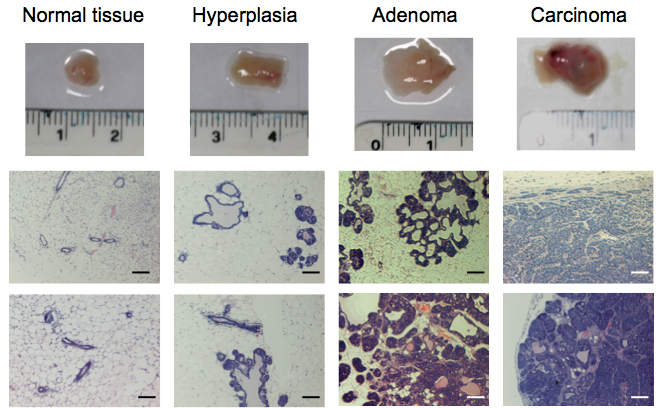

Note: For normal mammary gland isolation, mammary tissue of MMTV-PyMT negative females of 10 weeks of age is dissected. For isolation of hyperplastic tumors, mammary tissue of MMTV-PyMT positive females of 6 weeks of age is dissected. For isolation of adenoma, carcinoma, and invasive carcinoma, mammary tissue of MMTV-PyMT positive females of 7, 8 and 10 weeks of age, respectively, is dissected (Figure 1). These time points may vary. For more information about the determination of the correct age and tumoural stage, please read Note 2 at the end of the protocol. - Samples are moved into a laminar flow tissue culture hood under sterile conditions.

- Tissue samples are carefully analysed checking for signs indicative of their tumoral stage. As a rough guide, normal tissue appears fatty and soft. Hyperplastic tissue appears considerably enlarged but still fatty and soft. Adenoma, carcinoma, and invasive carcinoma appear enlarged, stiff and multimodular to variable degrees (Figure 1).

Note: As a result of the multimodular aspect of this type of tumour, special care must be taken in order to use and analyse only single modules. This is highly important if you want to make sure that you are isolating cells from a specific stage as individual modules may have progressed to different tumoral stages. The size of the modules varies with tumour size, age, localization and between individual mice. Expert pathological advice is recommended (see Notes 2-3). - For each single module, take one part for histopathology analysis and one part for isolation of fibroblasts. For histopathological analysis, the sample is fixed in 10% NBF overnight at 4 °C. See Figure 1 for representative hematoxylin and eosin staining of tissues.

Figure 1. Representative tissue samples and hematoxylin and eosin staining of tissues from normal FVB/n mammary glands and progressive breast tumoural stages (hyperplasia, adenoma and carcinoma) from the MMTV-PyMT model. Scale bars represent 100 µm.